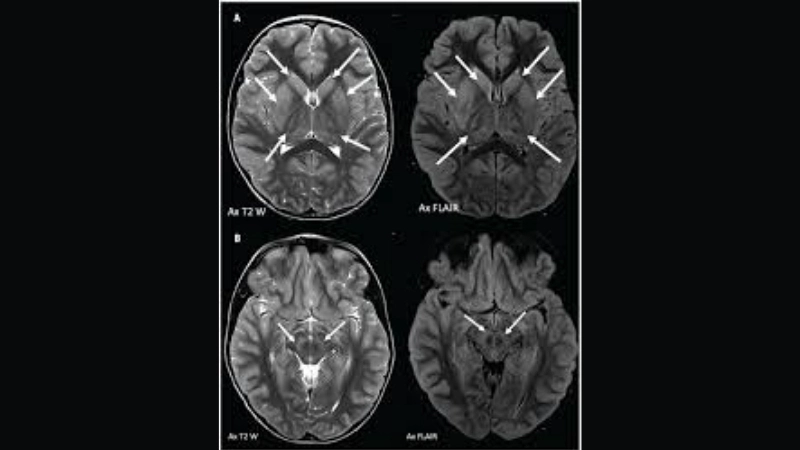

Image description of Powassan Encephalitis

Powassan Encephalitis is a rare, tick-borne viral infection that affects the brain. It can cause fever, headache, and severe neurological complications if left untreated.